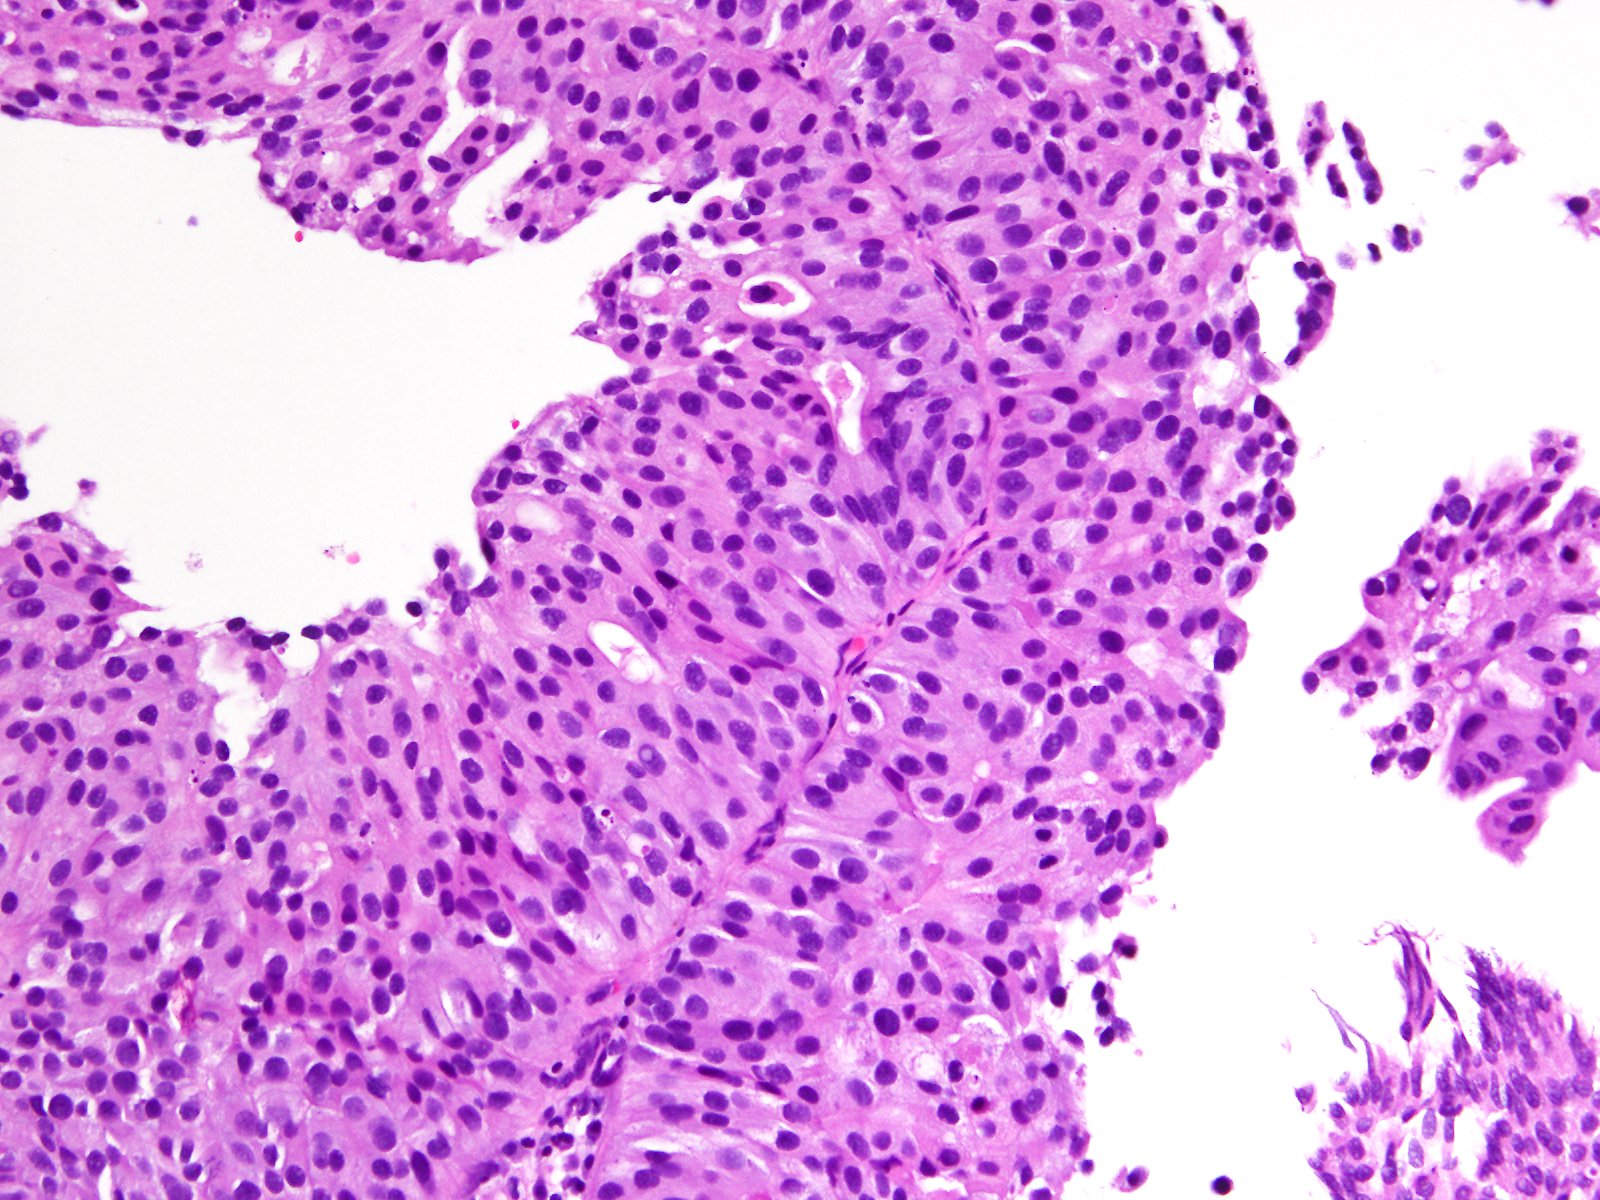

Bladder Papillary Lesions

Case ID: 357

13 Oct, 2015